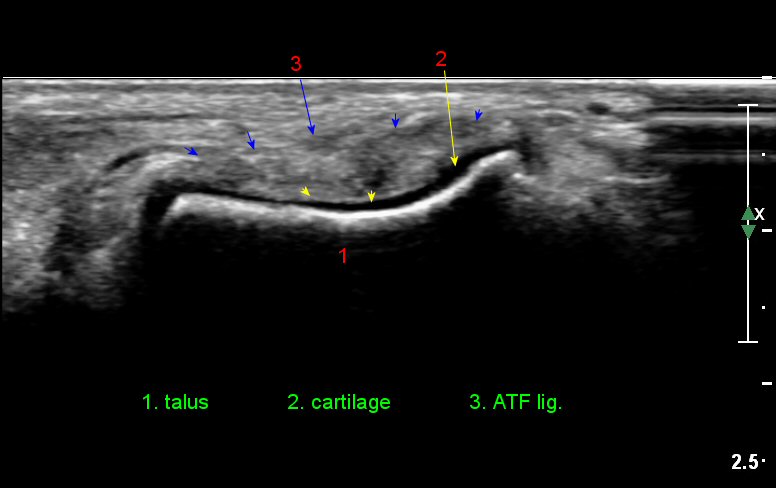

¹ß¸ñ°üÀý ¾ÕÂÊ Á¾´Ü¸é°Ë»ç¿¡¼­ ƯÀÌ ¼Ò°ßÀ» º¸ÀÌÁö ¾ÊÀ¸³ª(»çÁø 1)

ŽÃËÀÚ¸¦ ÀÎÁ¢ÇÑ ºÎÀ§·Î À̵¿ÇÏ´Ï ¼Ò·®ÀÇ °üÀý³» ¼ö¾×Àú·ù°¡ °üÂûµÈ´Ù(»çÁö 2).